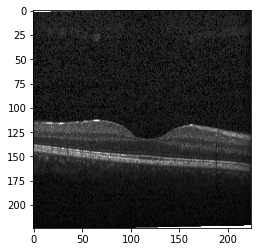

Original Image

Original Image

Original Image

Fig 6, 7, 8 and 9 depicts the visualization of correct predictions by our proposed CNN model where fig 6 is class CNV, fig 8 is class DME, fig 7 is DRUSEN and finally, fig 9 is NORMAL. Here the first photo in every class is the original image. The LIME map of our suggested model’s prediction is shown in image B whereas in image C the positive region is highlighted in specific sections on the original image. For Image D we have increased the number of features from 5 to 10 thus more regions have been predicted as the positive region which is highlighted in green. After increasing the features from 5 to 10, some of the regions are predicted wrongly. The red regions represent the output of incorrect prediction. The following image represents the Grad-CAM heatmap highlighting the regions with our model’s prediction.